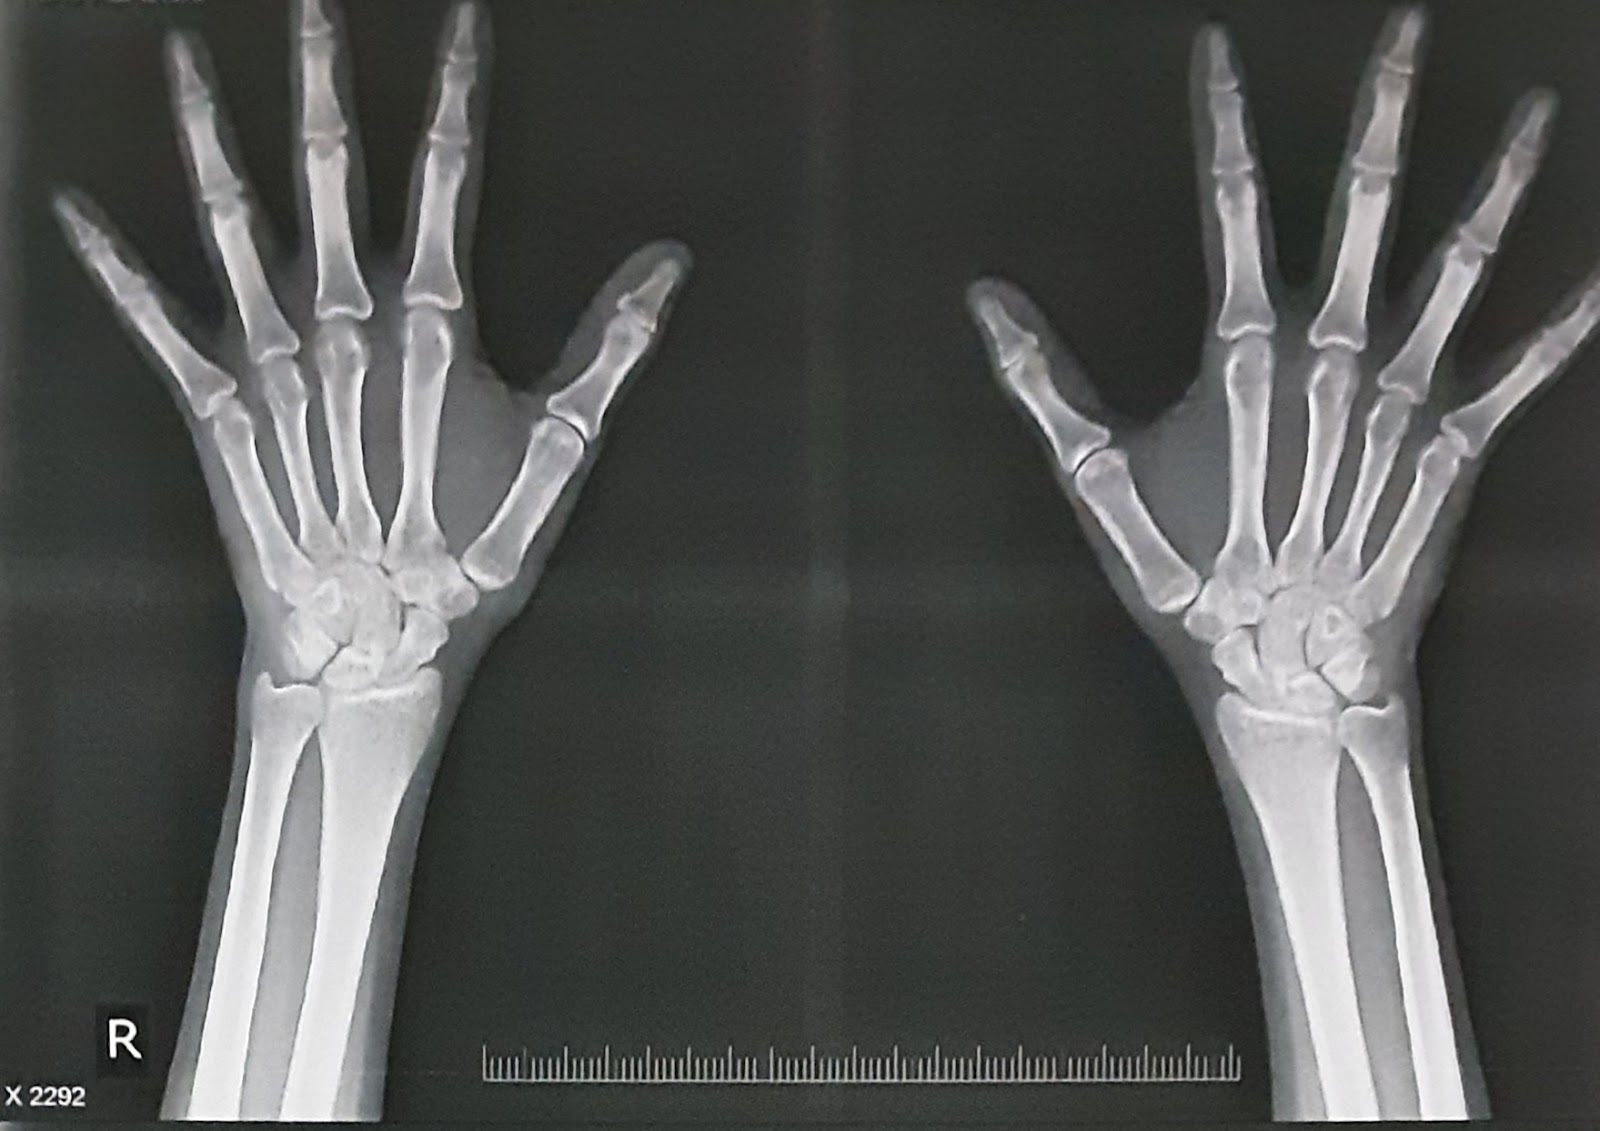

18 year old female with FEVER AND POLYARTHRITIS

18 year old female with FEVER and POLYARTHRITIS.

Patient was apparently asymptomatic 2 months back then she developed fever, following which fever was subsided and the patient started having pain in the small joints PIPI,DIP,MCP joints,subsided with medication and relapsed after stopping medication. Now she has fever with multiple joint pains ( small joints of hands,elbow,shoulder,) .Patient had history of migratory polyarthritis ,history of dragging type of pain in the both lower limbs. ( Ankles and joints of foot are spared).

INVESTIGATIONS